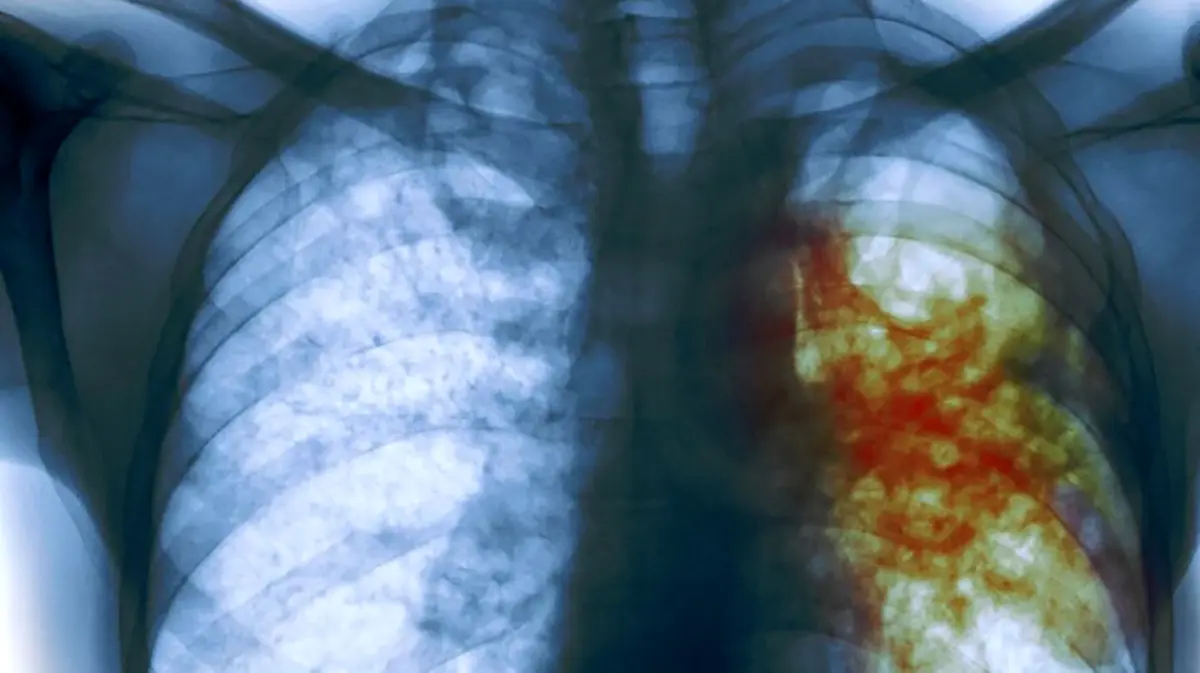

4. رادیوگرافی قفسه سینه (X-ray Chest)

روش: انجام رادیوگرافی قفسه سینه برای شناسایی علائم فیزیکی سل در ریهها.

نتیجه: در این تصویر، ممکن است لکهها یا تغییراتی در ریهها مشاهده شود که نشاندهنده وجود عفونت سل باشد.

مزایا: این روش برای تشخیص سل ریهای بسیار مؤثر است و به پزشک کمک میکند تا تصمیمات درمانی مناسبی اتخاذ کند.